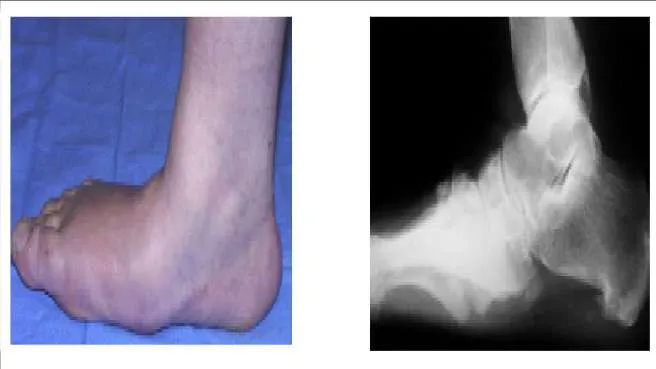

A 66-year-old woman has experienced the gradual onset of a flatfoot deformity over the past 10 years. She notes that the condition is bilateral, although worse on one side. Presented are clinical and radiographic images of her condition. This is associated with pain upon ambulation and difficulty with shoe wear. The most likely cause of this flatfoot deformity is:

Correct Answer: Tarsometatarsal arthritis

Although posterior tibial tendon insufficiency is a more common cause of adult acquired flatfoot, in this patient the associated clinical and radiographic deformity makes the diagnosis of tarsometatarsal arthritis more likely.